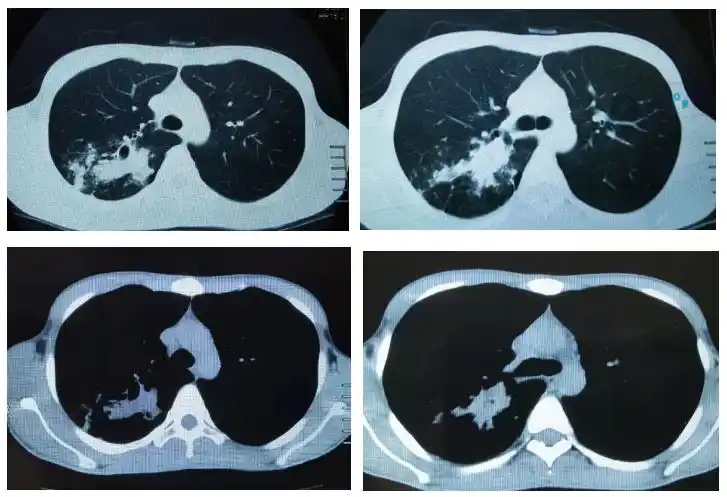

从ct上判断肺结核传染性的三种征象

多发小结节状卫星灶的肺结核

陈起航教授肺结核的影像学评价遏制终止终结肺结核2